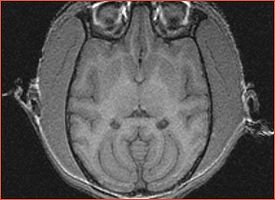

Zero filling artifact

Susceptibility artifacts